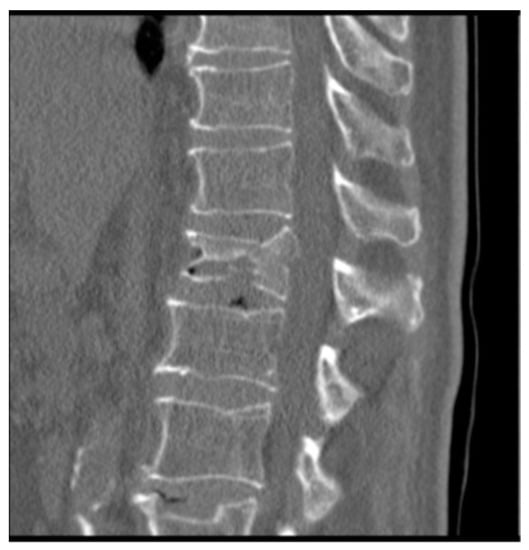

2.2. Evaluation of Anatomical Restoration

To know the vertebral height restoration in fractures after vertebroplasty, there exists no unanimous methodology. Moreover, existing methods are imprecise and can lead to great variability. Therefore, it is necessary to define a method that can be used to evaluate anatomical restoration. In our study, we have used 3D technology, that is definitive in this proposed new treatment [12,18,37]. The method has been developed by LBM ENSAM (Paris, France) to quantify the anatomical restoration. The exploration and interventions were carried in the Hospital Clínico Universitario de Valladolid. We have used a system: Revolution General Electric spectral CT, Healthcare. The protocol to be followed was based on the following parameters: tube voltage: between 80 and 140 kVp, milliamperage: 190 mA, rotation time: 0.8 s, pitch: 0.516, slice thickness: 0.625 mm, ASIR-V-40%, ASIR-V-40% and ASIR-V-40%. From millimetre axial slices of CT scans, 3D reconstructions were obtained using a segmentation technique (Figure 1 and Figure 2).

Male, 71-year-old, retired, affected by an osteoporotic bony condition. He experienced pain (9.1 on VAS scale) after a biconcave fracture in L1 (Figure 5). The imaging assessments showed that the two endplates have been affected by the fracture.

Figure 5.

CT with both end plates impacted of the L1 vertebra.